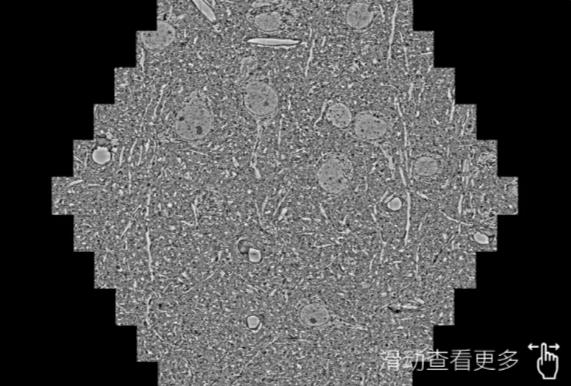

鼠脑切片。左图使用江津蔡司江津扫描电镜MultiSEM706对165μmx143pm面积区域成像,耗时仅需1.5秒。右图为鼠脑切片中30μm区域放大效果。样品由芝加哥大学B.Kasthuri提供。

使用蔡司高速江津扫描电镜MultiSEM对1mm²人脑皮层组织进行高分辨成像,并对其中的各种细胞结构进行三维重构分析。左图展示了2x3mm²组织平面中锥体神经元的三维重构效果。右图显示了局部体积神经元三维重构。图像由哈佛大学chtman实验室提供,渲染图由D. Berger 制作。